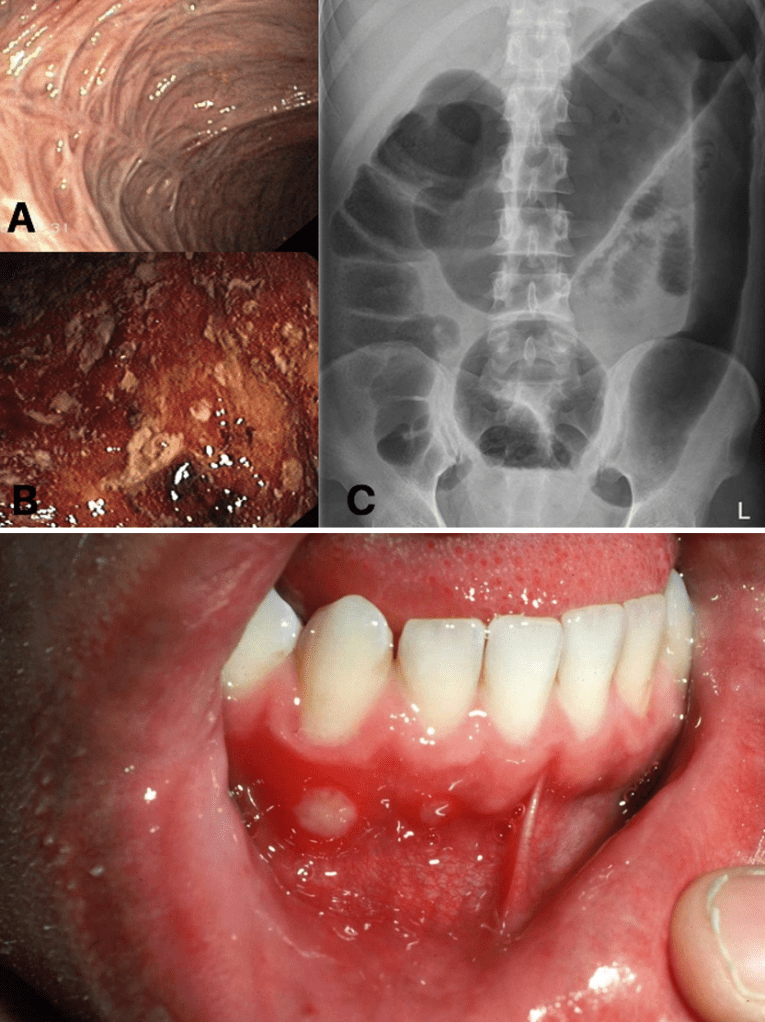

Answer: C) Ulcerative Colitis

Explanation: Ulcerative Colitis is a chronic inflammatory condition of the colon characterised by continuous superficial inflammation in the colon, predominantly the sigmoid colon. Symptoms include bloody diarrhoea, abdominal pain, aphthous ulcers, and tenesmus. Colonoscopy shows continuous inflammation confined to the colon and plain films highlight the loss of haustra in the colon.

Aphthous ulcers